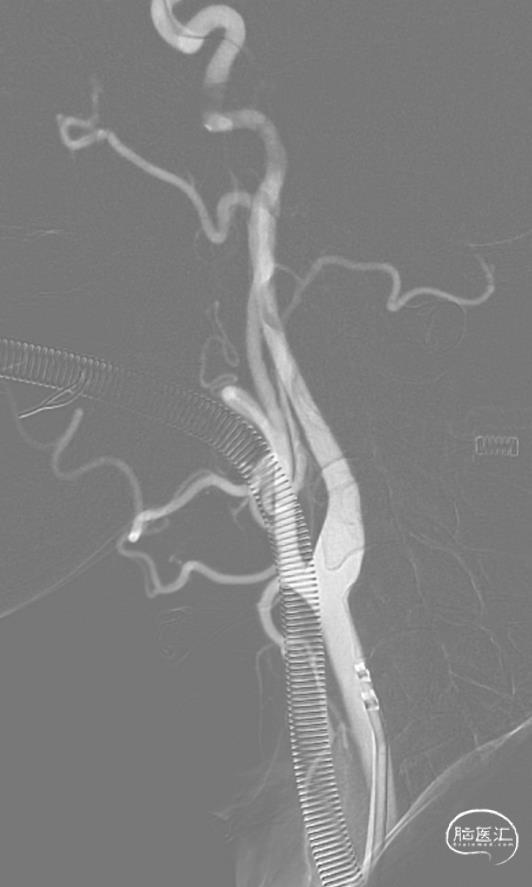

弓上造影:II型弓

超选右侧ICA正位及侧位造影